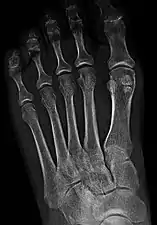

- One or both of the sesamoid bones under the first metatarsophalangeal joint (of the great toe) can be multipartite – in two or three parts (mostly bipartite – in two parts).[12]

Bipartite medial sesamoid bone under the first metatarsophalangeal joint of the great toe of the left foot of an adult woman.